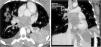

A healthy 25-year-old woman was admitted to the emergency department with a three-week history of gradual dyspnea on exertion, asthenia and weight loss. One week before admission, her dyspnea had worsened and had also presented at rest, with cough and hemoptysis, so she decided to seek medical attention. Physical examination revealed a mid-diastolic cardiac murmur. The transthoracic echocardiogram showed a large mass with irregular echogenicity filling the whole of the left atrium. Transesophageal echocardiography was performed and revealed the mass in the left atrium prolapsing into the left ventricle during diastole and causing mitral valve obstruction (Fig. 1A; Online Videos A–C). Continuous-wave Doppler ultrasound indicated severe mitral valve obstruction (mean gradient of 16mmHg) (Fig. 1B). The study also revealed extension into all the pulmonary veins (Fig. 1C). A computed tomogram of the thorax was performed and confirmed the diagnosis (Fig. 2; Online Video D). Cardiac surgery was performed with complete tumor resection (Fig. 3). The histopathological examination with immunohistochemical stain (Fig. 4A), hematoxylin–eosin stain (Fig. 4B) and electron microscopy (Fig. 4C) showed an undifferentiated pleomorphic sarcoma (pleomorphic malignant fibrous histiocytoma). The patient started chemotherapy and was discharged 17 days after surgery. Unfortunately, twenty days after discharge, she was readmitted to the hospital because of headache. Cranial computed tomography revealed multiple intracranial lesions suggestive of metastases. She underwent 10 sessions of holocranial radiotherapy. Six months after surgery she is alive but multiorgan metastatic disease has been demonstrated.